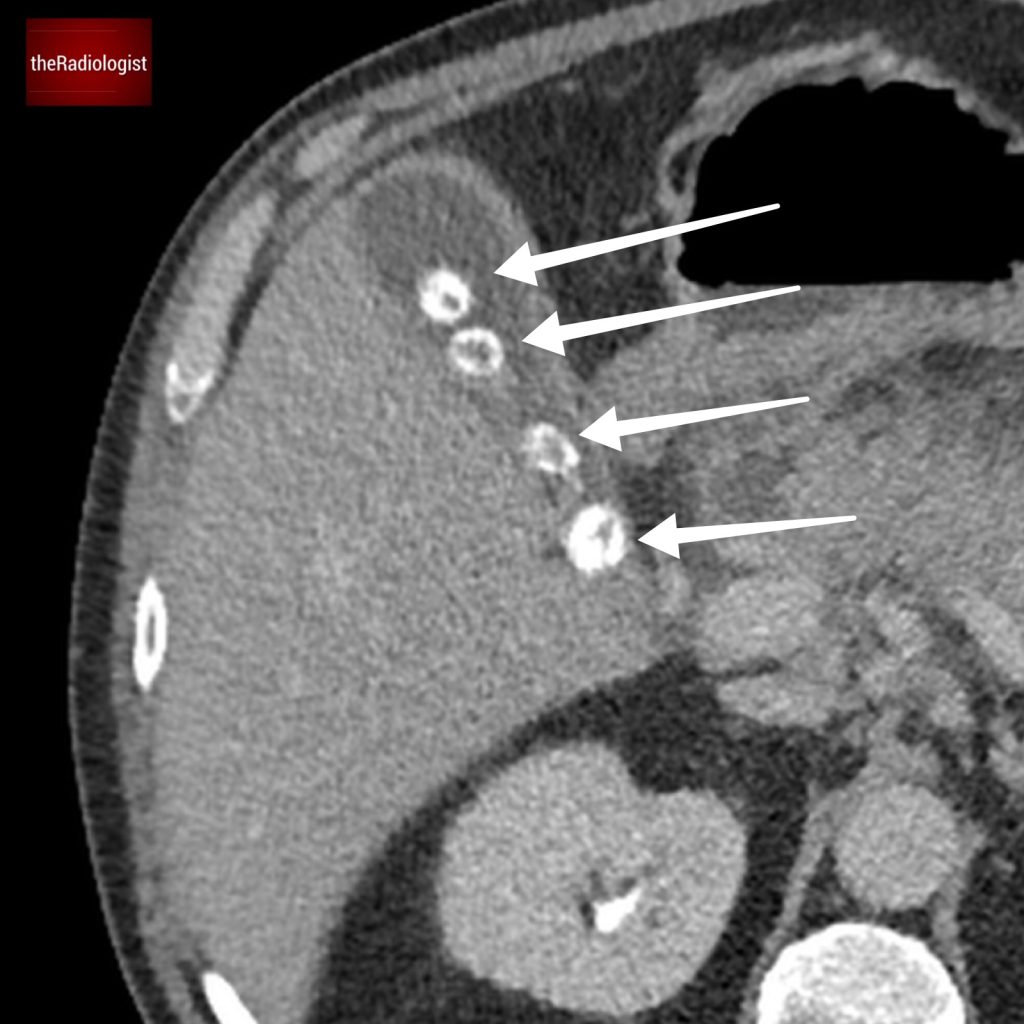

On a follow up MRI scan 2 months later we can see the right psoas is now returning to normal.

The patient was treated with a long course of antibiotics and we saw a good response on imaging with improvement in the right psoas abnormality at 2 months.